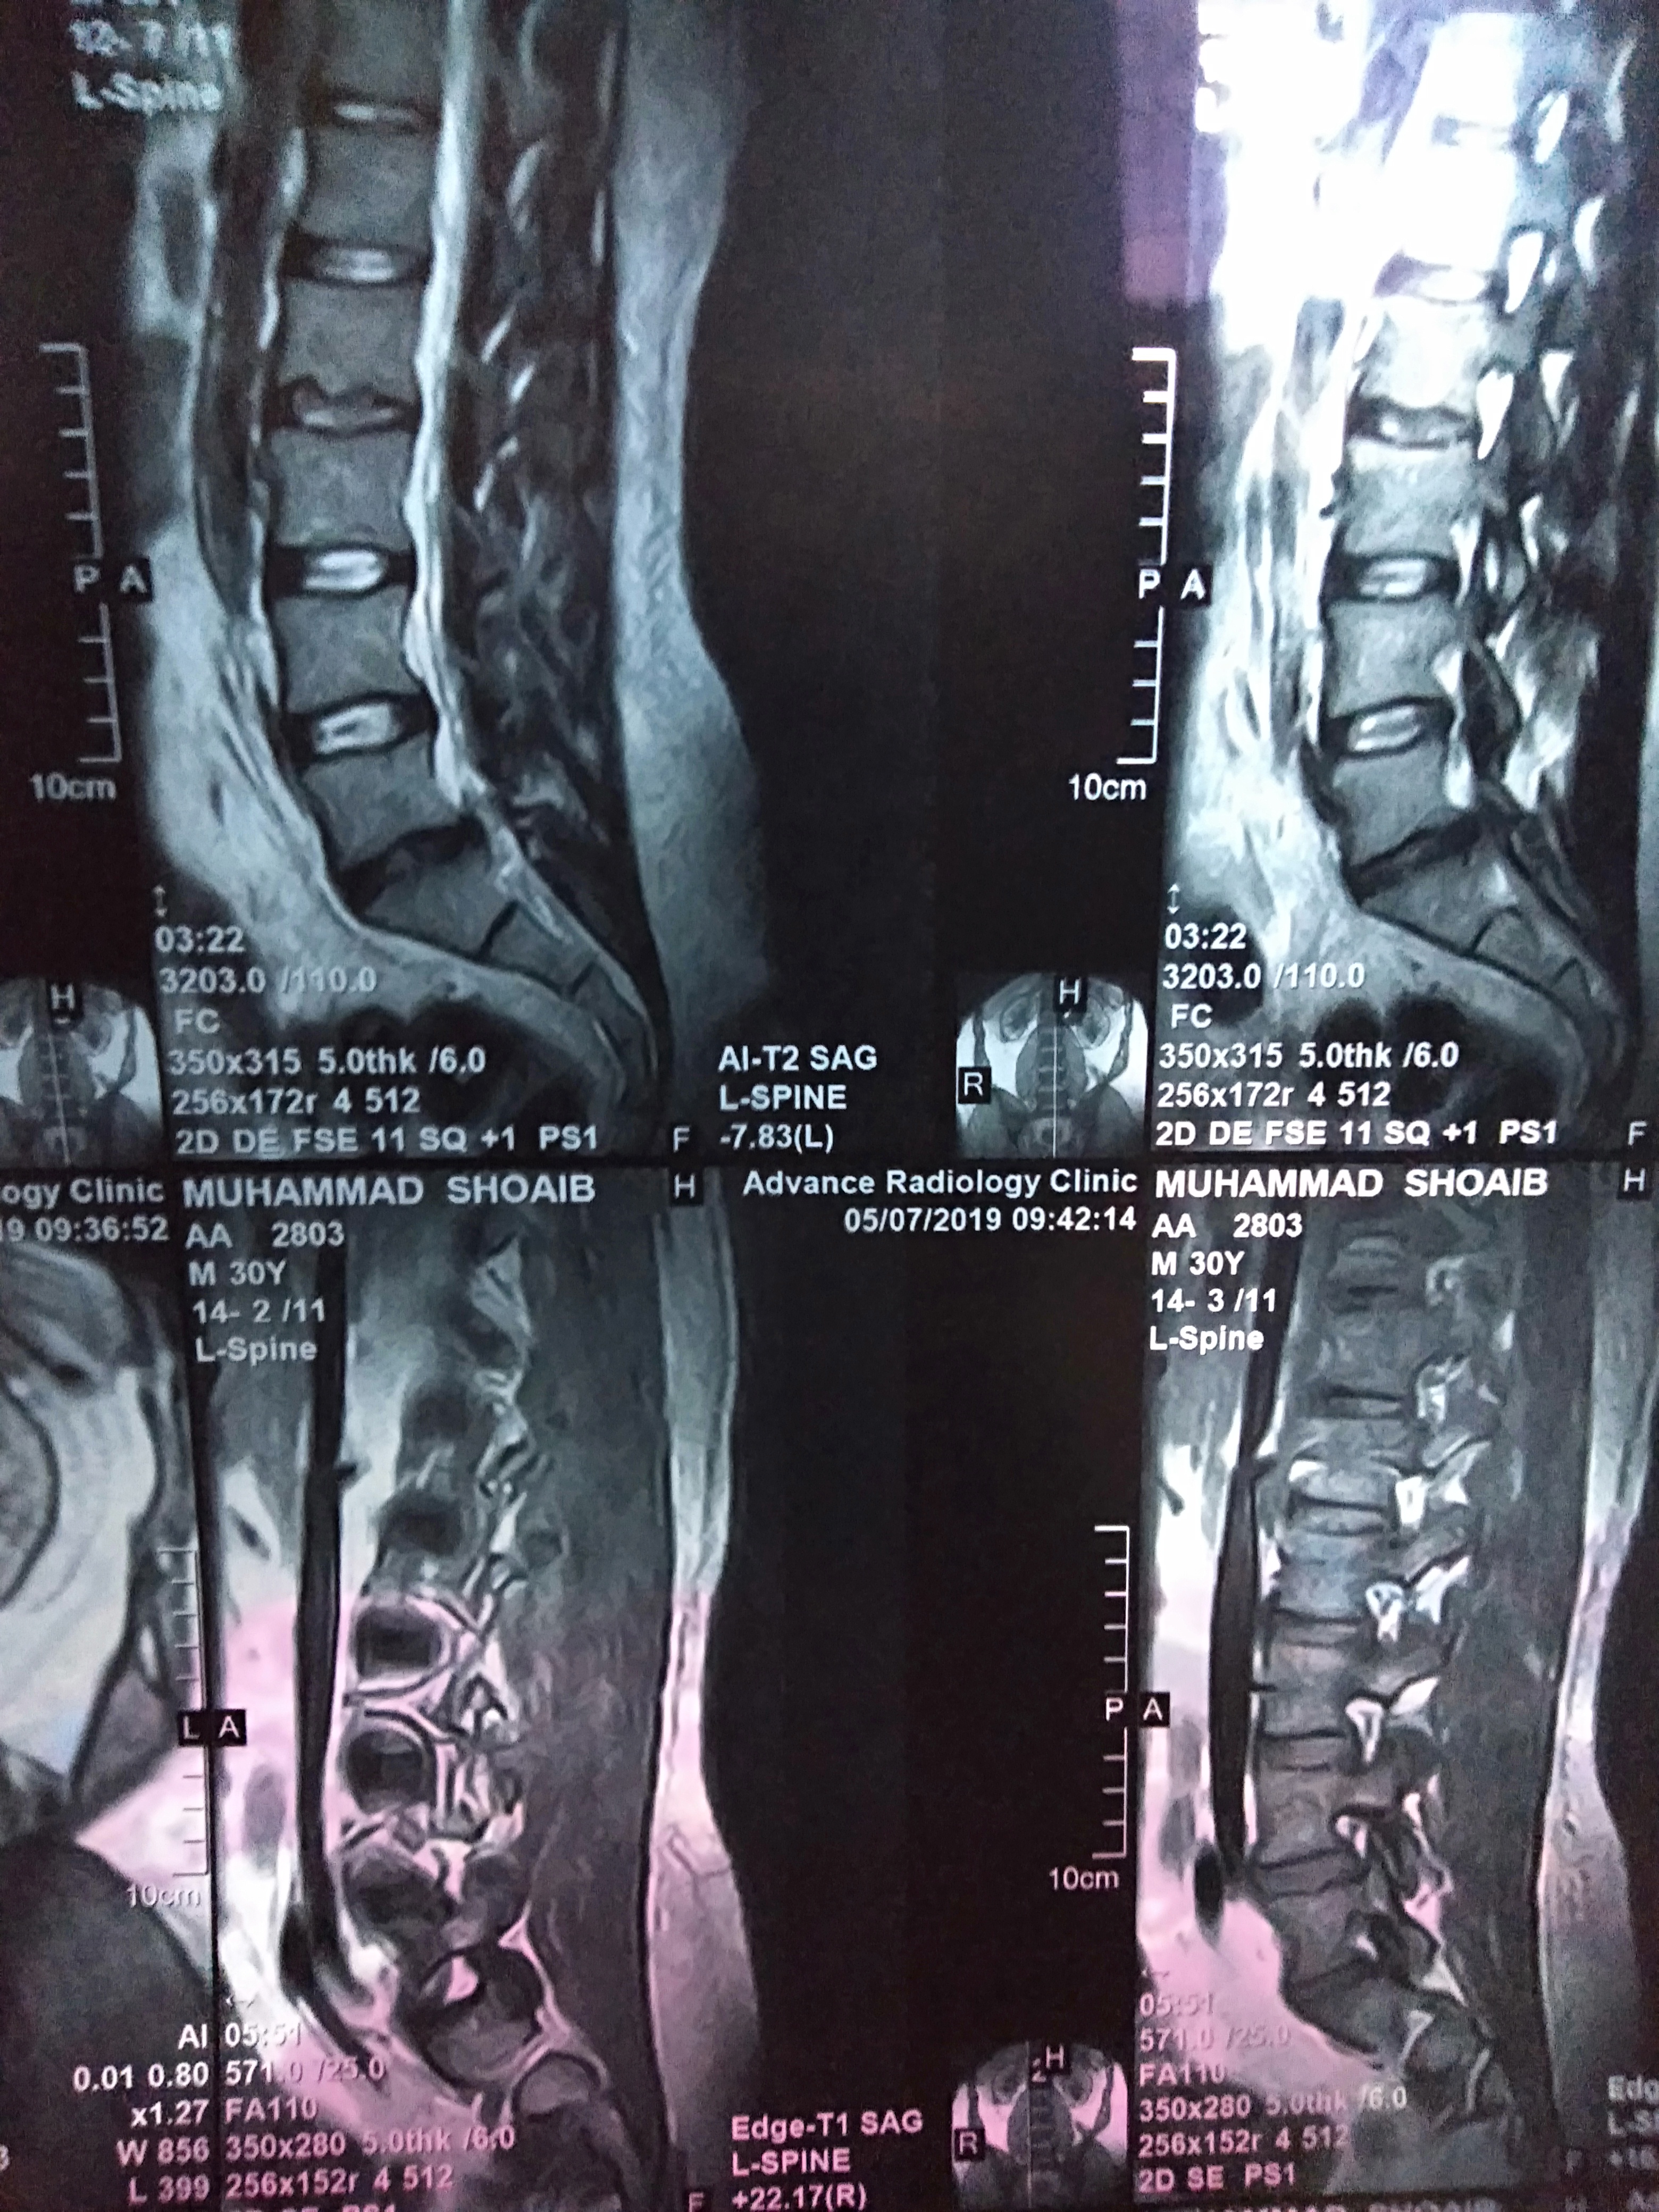

On 30nth April I was suffering from sever back and leg pain, after a day the pain was gone by taking some pain killers.. but day after tomorrow my thighs heel became numb .. And after MRI of lumbar sacral region and as per neurosurgeon Diogenes I have an problem in l5 s1 which disc is suggested me a surgery in first visit.. and a injection called epidural steroid injection ... I am scared from surgery and from this injection by reading of its risks from different internet channels ...